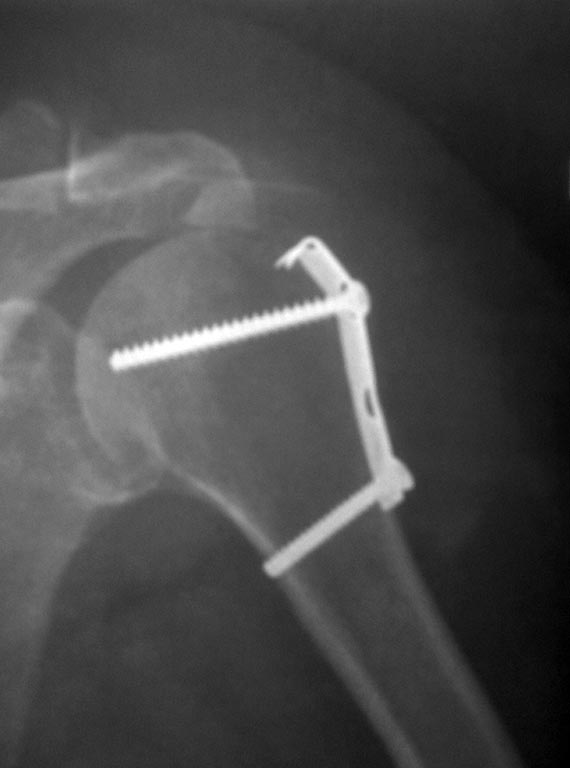

Коллеги! Подскажите, пожалуйста марку металла и фирму производителя

представленной металлоконструкции! По понятным причинам возникла

необходимость в МРТ и лучевых диагностов интересует этот вопрос.

Пациентка оперирована в другой больнице. Заранее признателен!